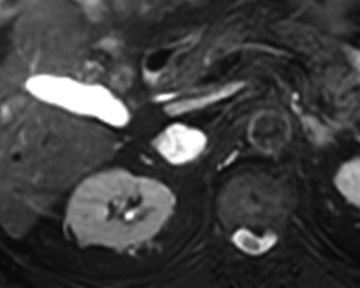

Adrenal Adenoma. An adrenal adenoma is a benign (noncancerous) tumor that forms in your adrenal glands. It's the most common type of adrenal gland tumor. Most adrenal adenomas don't produce symptoms or require treatment. However, some adenomas may cause your adrenal glands to secrete excess hormones, like cortisol.

Adenoma. This is the most common type of adrenal gland tumor. Adenoma is also called an adrenocortical adenoma. It is a noncancerous tumor of the adrenal cortex that can be functioning or nonfunctioning.

Where is adrenal adenoma?

You have two adrenal glands, one located above each kidney. Each gland contains two tissue types: the cortex and the medulla. Benign adrenal tumors that develop in the cortex are also called adrenal adenomas. Those that develop in the medulla are also called pheochromocytomas (fee-o-kroe-moe-sy-TOE-muhs).

How is adrenal adenoma diagnosed?

In addition to a physical examination, the following tests may be used to diagnose an adrenal gland tumor: Blood and urine tests. Blood and urine tests help measure the amount of adrenal hormones, which can tell the doctor if the tumor is functional or nonfunctional. A 24-hour urine sample may also be needed.